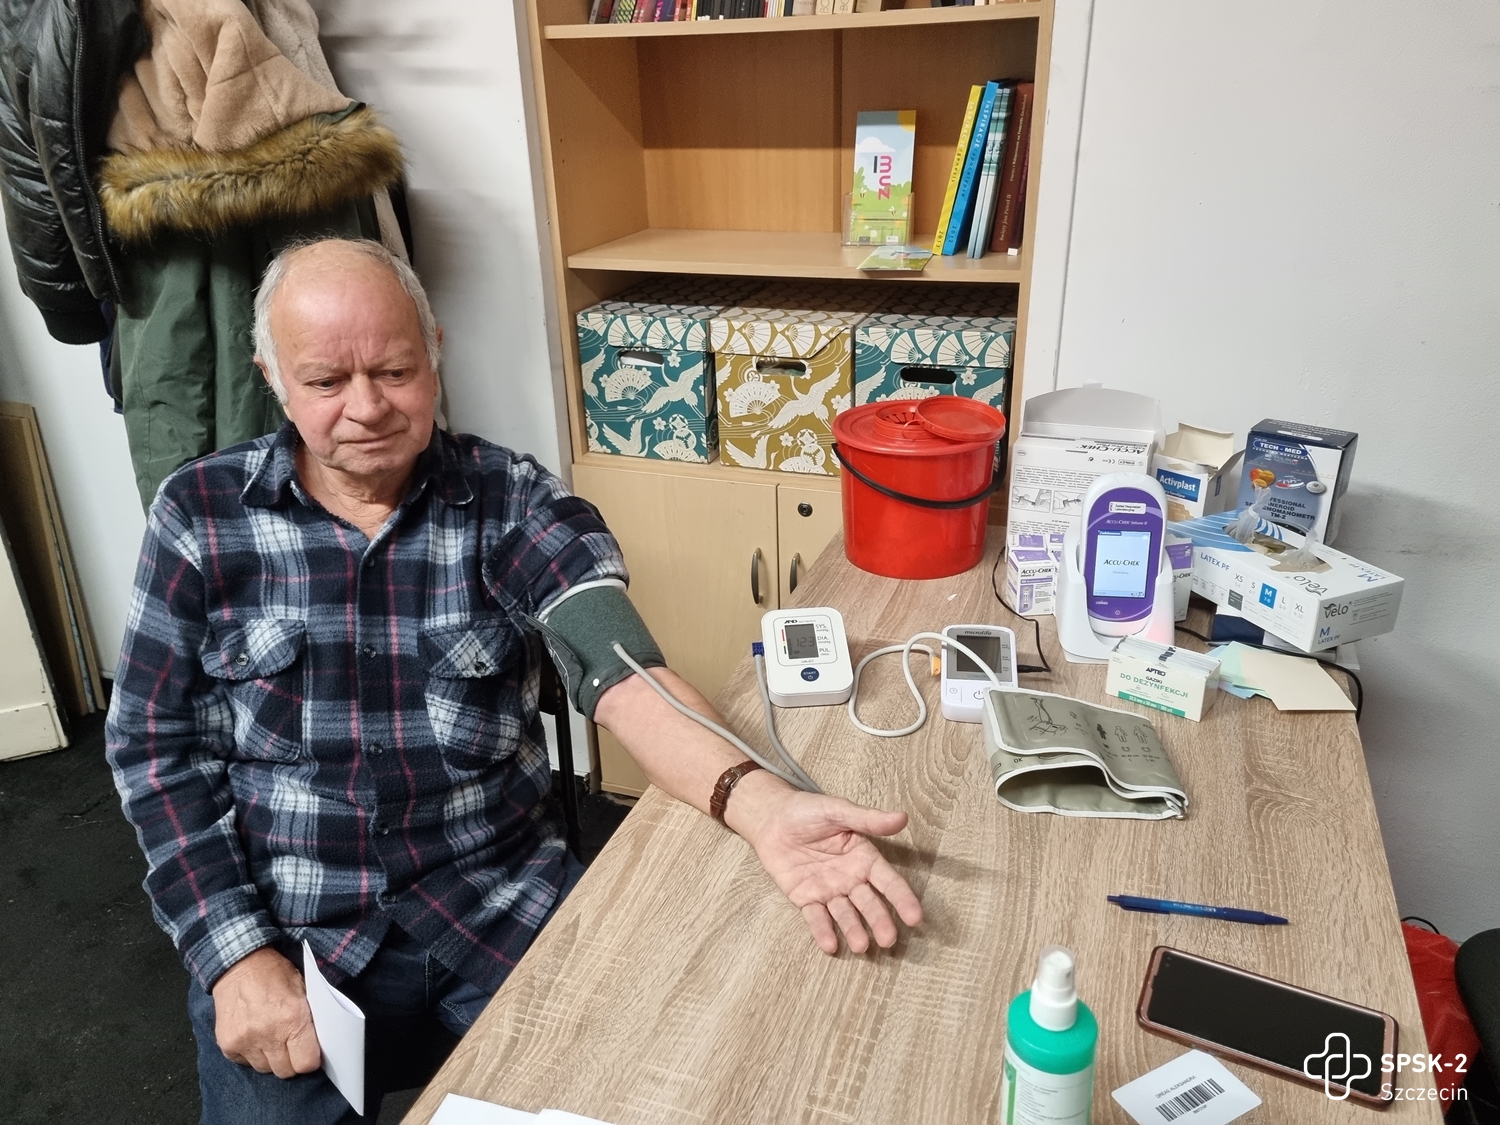

Badania przesiewowe aorty organizowane w ramach Dnia Zdrowia Aorty cieszyły się ogromnym zainteresowaniem. Pierwsi chętni do badań ustawili się w kolejce do zapisów już po godz. 8. U żadnej z osób nie wykryto tętniaka. Ta grupa pacjentów może spać spokojnie.

USG Dopplera aorty przeprowadzali dr n. med. Miłosz Kawa i dr n. med. Maciej Wojtuń. Grupą docelową, do której skierowane były badania były osoby po 65. roku życia, u których stwierdzono jednocześnie trzy spośród następujących czynników ryzyka sercowo-naczyniowego: choroba wieńcowa, palenie tytoniu, nadciśnienie tętnicze, hiperlipidemia, płeć męska, występowanie tętniaka aorty brzusznej u rodziców lub rodzeństwa czy przewlekła obturacyjna choroba płuc.

Oprócz badań USG chętni mogli zaznajomić się z najnowszymi metodami leczenia tętniaków aorty, obejrzeć filmy, w których nasi chirurdzy naczyniowi opowiadają o zagrożeniach chorobami naczyniowymi, zobaczyć na własne oczy czym jest tętniak i jak wygląda, obejrzeć wydrukowane w Ośrodku Technologii Medycznych 3D naszego szpitala modele organów człowieka, oraz poczuć się jak chirurg podczas operacji i dzięki goglom Hololens i wyświetlanemu w nich obrazowi rozszerzonej rzeczywistości ponawigować obrazem tomografii komputerowej i dokładnie obejrzeć struktury anatomiczne człowieka.

Pielęgniarki i położne naszego szpitala: Aleksandra Dreas, Alicja Kapała, Klaudia Kokoszka, Ewa Kubiak oraz stażyści i studenci Pomorskiego Uniwersytetu Medycznego w Szczecinie: Katarzyna Czarnecka, Karolina Kalembkiewicz, Michał Kargul, Dominika Kucharska, Karolina Seidler, Urszula Sielicka, Patryk Skórka, Claudia Wietrzykowska mierzyli ciśnienie, poziom glukozy we krwi i przeprowadzali wstępną kwalifikację pacjentów do badań oraz pokazywali jak rozszerzona rzeczywistość pomaga zobaczyć to, czego nie widać gołym okiem. Dr n. med. Paweł Rynio, chirurg naczyniowy i kierownik projektu – chętnie opowiadał o chorobach naczyniowych i tłumaczył m.in. jak technologia druku 3D wspiera medycynę.